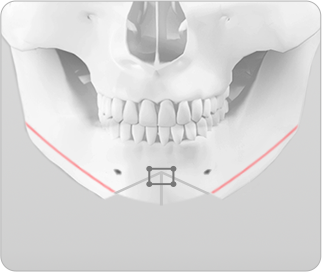

기존의 효과 없는 T절골술

• 턱끝의 모양이 자연스럽지 않으며 튼튼하지 않고 부작용 발생 가능성 높음

기존 T 절골술의 경우 턱끝을 T자 모양으로 절제하고 모아서 고정하는 방법으로 턱끝의 길이와 넓이를 효과적으로 조절할 수 없으며, 턱끝이 넓은 U자 모양이 되거나 울퉁불퉁한 경우가 있습니다. 그리고 절골선이 신경과 치아뿌리에 가까워 수술 후 부작용 발생 가능성이 있습니다.